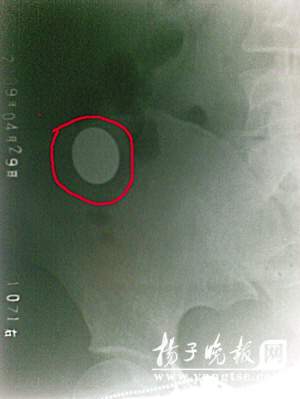

經X光片檢查,何小姐腹中有一枚一元硬幣,幸運的是它已穿過消化道最狹窄的胃幽門進入大腸,如不出意外,過幾個小時,就可排出體外。外科的孫主任說,金屬異物進入腸道被蠕動和摩擦,極有可能發(fā)生腸穿孔和出血,最好及時就診。就此事,記者采訪了江蘇省雜技家協(xié)會理事、魔術俱樂部主任方振勇。他說,魔術“吞硬幣”是簡單的小魔術,它重在手法和手技,魔術師將硬幣放入口中只是個假動作,然后將硬幣從別的地方拿出來,對于初學者,如果沒有掌握要領,不要輕易自創(chuàng)和模仿。(任國勇)